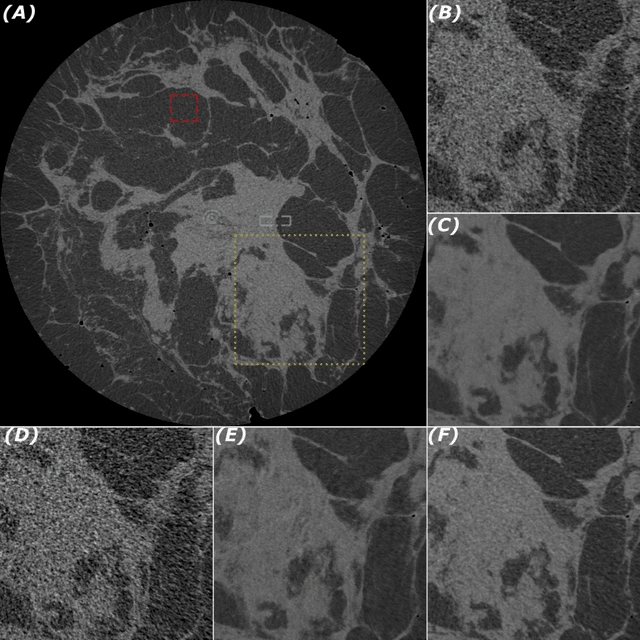

Abstract:Breast cancer is the most frequently diagnosed human cancer in the United States at present. Early detection is crucial for its successful treatment. X-ray mammography and digital breast tomosynthesis are currently the main methods for breast cancer screening. However, both have known limitations in terms of their sensitivity and specificity to breast cancers, while also frequently causing patient discomfort due to the requirement for breast compression. Breast computed tomography is a promising alternative, however, to obtain high-quality images, the X-ray dose needs to be sufficiently high. As the breast is highly radiosensitive, dose reduction is particularly important. Phase-contrast computed tomography (PCT) has been shown to produce higher-quality images at lower doses and has no need for breast compression. It is demonstrated in the present study that, when imaging full fresh mastectomy samples with PCT, deep learning-based image denoising can further reduce the radiation dose by a factor of 16 or more, without any loss of image quality. The image quality has been assessed both in terms of objective metrics, such as spatial resolution and contrast-to-noise ratio, as well as in an observer study by experienced medical imaging specialists and radiologists. This work was carried out in preparation for live patient PCT breast cancer imaging, initially at specialized synchrotron facilities.

Abstract:Propagation-based phase-contrast X-ray imaging (PB-PCXI) generates image contrast by utilizing sample-imposed phase-shifts. This has proven useful when imaging weakly-attenuating samples, as conventional attenuation-based imaging does not always provide adequate contrast. We present a PB-PCXI algorithm capable of extracting the X-ray attenuation, $\beta$, and refraction, $\delta$, components of the complex refractive index of distinct materials within an unknown sample. The method involves curve-fitting an error-function-based model to a phase-retrieved interface in a PB-PCXI tomographic reconstruction, which is obtained when Paganin-type phase-retrieval is applied with incorrect values of $\delta$ and $\beta$. The fit parameters can then be used to calculate true $\delta$ and $\beta$ values for composite materials. This approach requires no a priori sample information, making it broadly applicable. Our PB-PCXI reconstruction is single distance, requiring only one exposure per tomographic angle, which is important for radiosensitive samples. We apply this approach to a breast-tissue sample, recovering the refraction component, $\delta$, with 0.6 - 2.4\% accuracy compared to theoretical values.